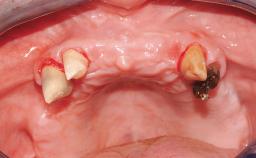

A 35-year-old Caucasian female presenting with advanced periodontal disease involving both the maxillary and the mandibular dentition was referred for evaluation. The patient, a non-smoker in good general health, requested treatment for recurrent periodontal abscesses, tooth mobility, and discomfort during chewing, as well as restoration of her missing teeth with a fixed prosthesis to improve mastication and esthetics. All residual maxillary teeth exhibited plaque deposits, deep pockets, bleeding on probing, and class III mobility and were evaluated as hopeless. All residual mandibular teeth except tooth 37 could be maintained after periodontal therapy.

Bone Volume Deficient vertically or deficient vertically AND horizontally